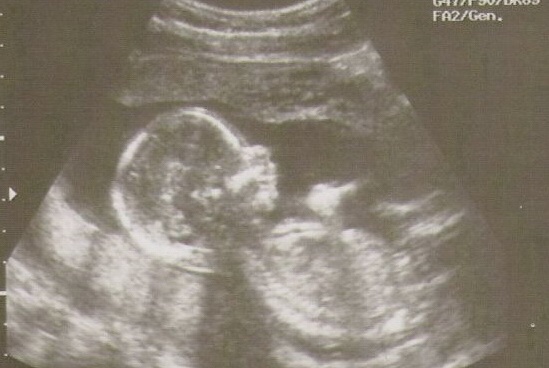

Bude to celý táta

KLUB TĚHULEK! VENDY Počasí se i u nás změnilo na urousané a upršené dny. Převařený mozek se trošku schladil a já tak nějak začínám fungovat. Těhotenství se strašně vleče, hlavně pro tak netrpělivého člověka, jako jsem já. Jsme v 19 týdnu a pořád žádný pohyb. Když jsme se stavili po týdnu na sono, malé si pěkně podřimovalo, ručku pod hlavou a nehodlalo se nám ani ukázat. Bude to lenoch a ještě k tomu stydlín. Pohlaví jsme tedy opět nezjistili a začínáme přemýšlet i nad tím, že se necháme překvapit.